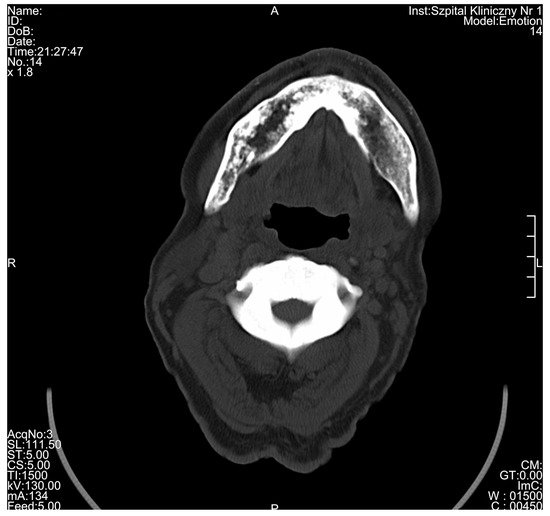

3. Results

| Radiological Feature | ADO Type I | ADO Type II | ADO Type III | Presented Case |

|---|---|---|---|---|

| General osteosclerosis | + | – | + | + |

| Skull vault osteosclerosis | + | – | + | + |

| Skull base osteosclerosis | – | + | – | + |

| Sandwich vertebrae (Ruger–Jersey spine) | – | + | – | + |

| Bone within bone | – | + | + | + |

| Hyoid sclerosis | – | – | – | + |